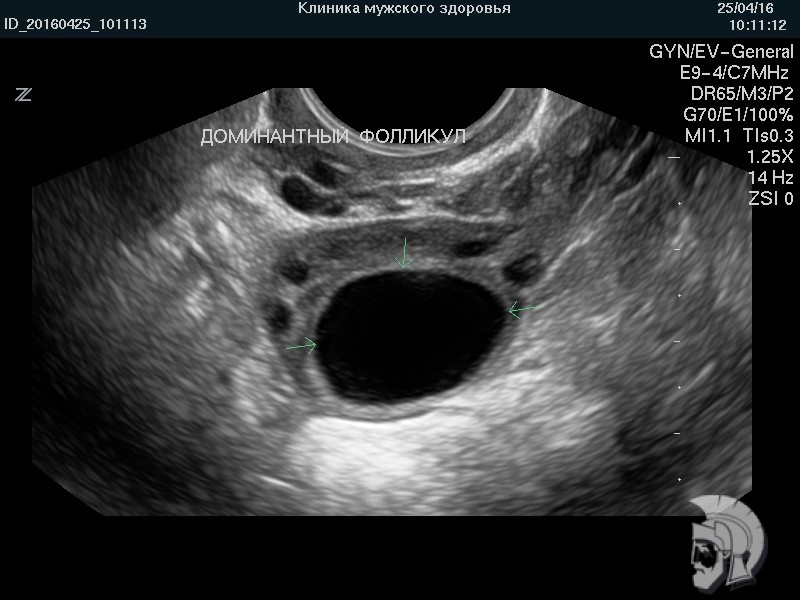

| Фото фолликулометрии. Созревший (преовуляторный) фолликул в яичнике указан стрелками |

| Фото фолликулометрии. Наиболее крупный фолликул (доминантный фолликул) указан стрелками |